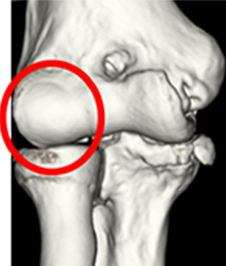

離断性骨軟骨炎の画像

肘の外側

(3D-CT)

離断性骨軟骨炎